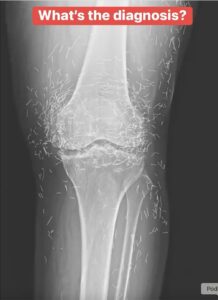

Acupuncture, an alternative treatment with a history spanning centuries, entails the insertion of needles into specific points on the body to alleviate pain or address various health issues. In this particular instance, the needles—likely crafted from gold—were deliberately left in her knees to provide ongoing stimulation.

He further cautioned that needles left embedded can interfere with X-ray interpretations. “The needles may obscure certain anatomical structures,” Guermazi remarked in 2013.

Even more troubling, needles that remain in the body can pose risks for future medical imaging. “The patient cannot undergo an MRI because needles left in the body might shift and injure an artery,” Guermazi noted.